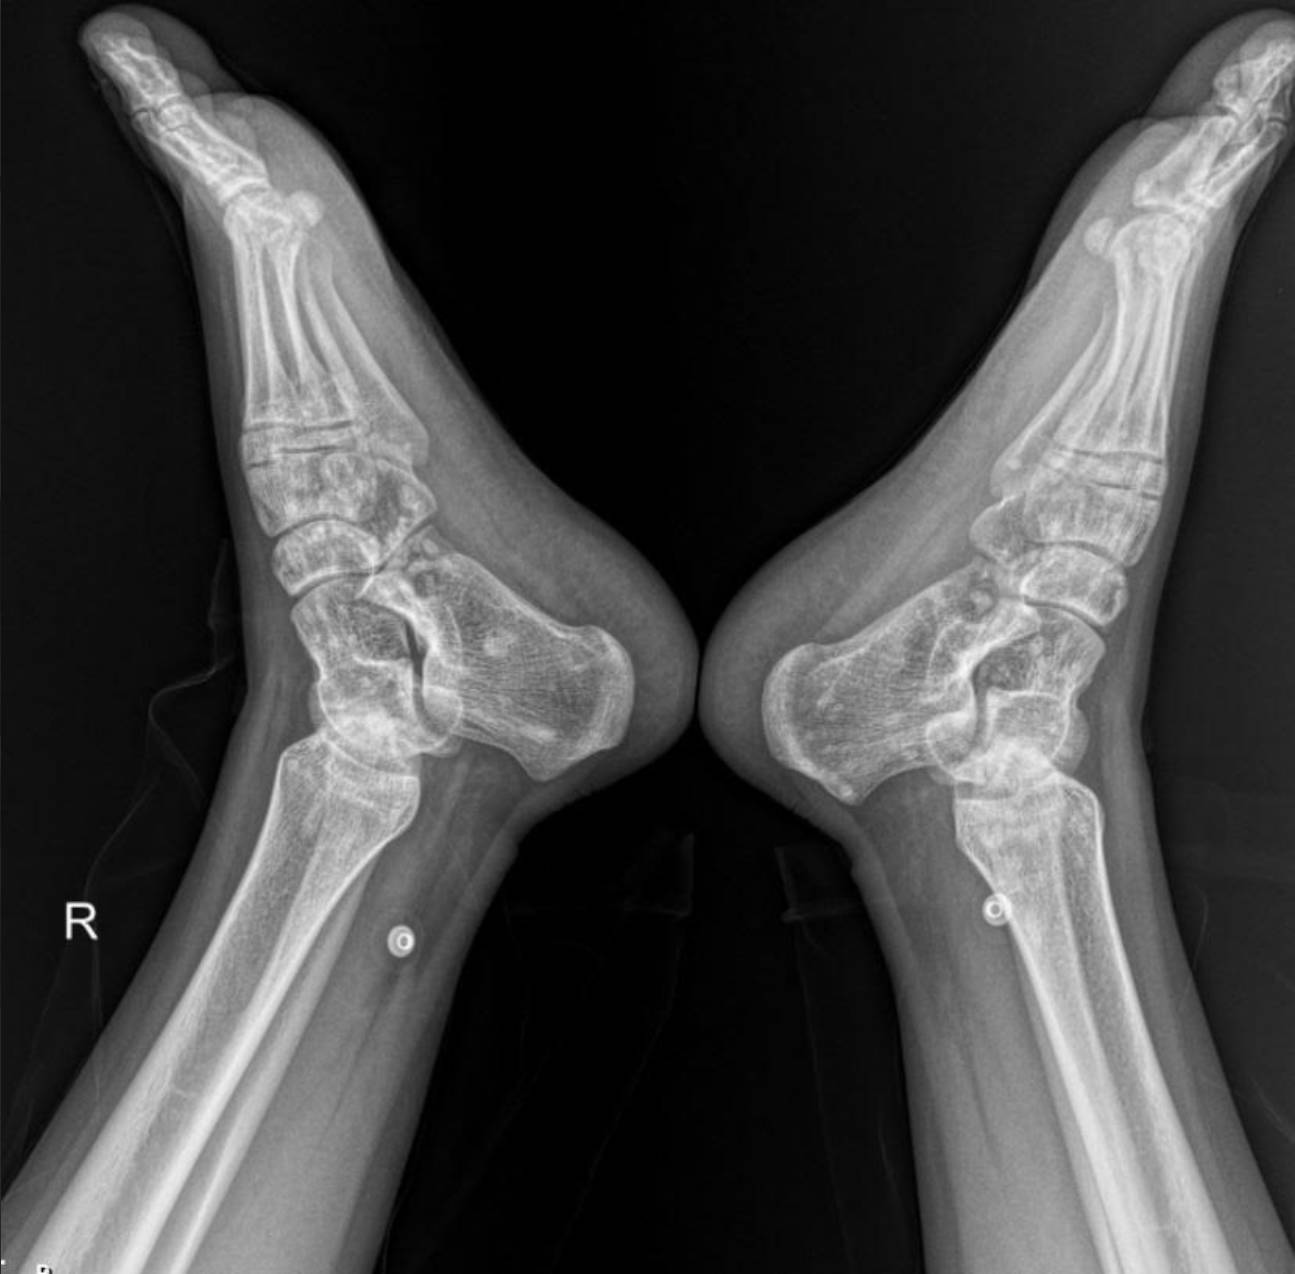

The X-rays of the pelvis, knees, elbows, wrists, and ankles demonstrate multiple, discrete, well-circumscribed sclerotic (densely opaque) lesions distributed symmetrically throughout the bones. These lesions are typically ovoid or spherical, varying in size, and are predominantly located in the epiphyses and metaphyses of long bones, as well as in the carpal and tarsal bones and the pelvic girdle.

Specifically:

- Wrists and Hands: The carpal bones, distal radius and ulna, and to a lesser extent, the metacarpals and phalanges, exhibit multiple small, dense foci.

- Ankles and Feet: The distal tibiae and fibulae, as well as the tarsal and metatarsal bones, show the characteristic sclerotic lesions.

These widespread, symmetrically distributed sclerotic bone islands are pathognomonic for hereditary osteopoikilosis (also known as osteopathia condensans disseminata). This condition is typically benign and often discovered incidentally. While not directly related to her renal artery stenosis or hypertension, its discovery is crucial for patient management as it can sometimes be associated with other connective tissue disorders, though often it is an isolated finding.